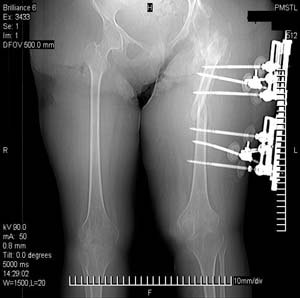

Можно наложить простейший аппарат таз-бедро и подвесить больного (он с ним и ходить сможет), а потом спокойно перемещать лоскуты.

>Можно наложить простейший аппарат таз-бедро и подвесить больного

Такая мысль тоже приходила. Не решились, так как:1.Выраженный остеопороз костей таза и бедра, больная тучная - высок риск того, что стержни не выдержат. 2.Сейчас больная передвигается в инвалидном кресле - хоть какая-никакая, а динамизация. Если лишить её этой возможности - застойная пневмония со всеми вытекающими...

>(он с ним и ходить сможет)

К сожалению, не сможет - у неё давнее повреждение спинного мозга с нижней параплегией